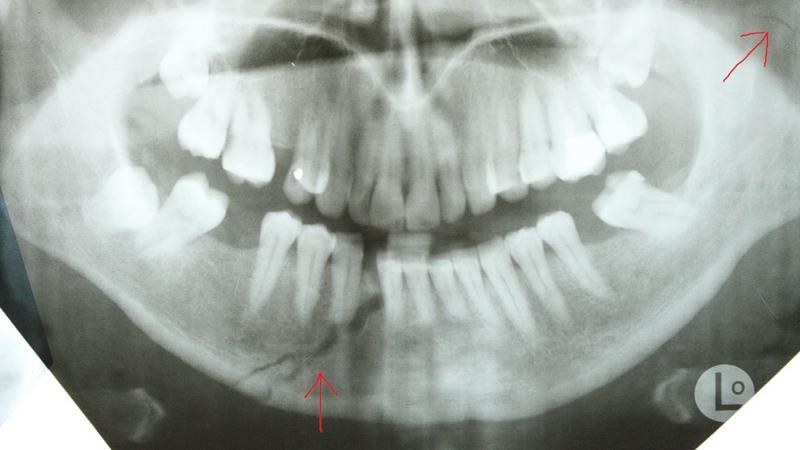

Перелом челюсти – это травма, которую можно заподозрить без использования специализированного оборудования. Однако для того, чтобы провести адекватное лечение и точно оценить степень повреждений, необходимо пройти детальное обследование у специалиста. После первичного осмотра врач назначит наиболее подходящие методы для выявления трещин. К примеру:

- рентгенографию;

- ортопантомографию;

- компьютерную томографию (КТ);

- магнитно-резонансную томографию (МРТ).